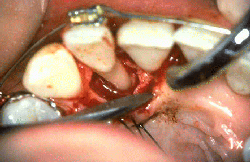

Mujer de 24 años de edad  que ha padecido  periodontitis juvenil desde los 16 años. Las lesiones periodontales se han tratado repetidamente durante los años precedentes y ella ha desarrollado una nueva  patología periodontal en el incisivo lateral derecho superior. Las profundidades de bolsa al sondaje de ese diente es de 4-10 mm  Un colgajo se ha levantado hasta la línea mucogingival y se ha expuesto el hueso maxilar. La pérdida de ligamento periodontal es severa en  mesial y distal  del lateral. En distal se observa un defecto óseo.

Otro colgajo se ha levantado en palatino. Se observa la pérdida del ligamento periodontal en  mesial y distal del lateral. Nótese el defecto óseo en forma de cráter en mesial del lateral.